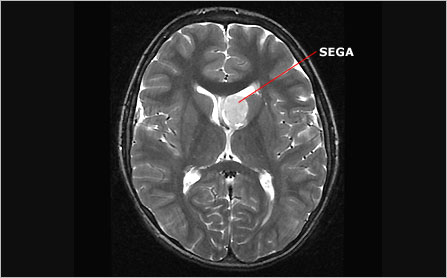

MRI showing SEGA

Axial brain MRI showing a SEGA

Subependymal giant cell astrocytomas (SEGAs) are large SENs. They too are benign tumors composed of undifferentiated, dysfunctional glial cells. However, because of their large size and their potential for continued growth, especially in children and adolescents, these lesions pose a significant risk. For reasons that are not well understood, the propensity for SEGAs to develop decreases dramatically after adolescence.

In rare cases, SEGAs grow large enough to obstruct the flow of cerebrospinal fluid through the lateral ventricles. This is more likely when they occur in particularly narrow passages such as the foramen of Monro, which carries fluid between the lateral ventricles and the third ventricle. Obstruction of this flow can cause a condition known as hydrocephalus, in which cerebrospinal fluid builds up causing the ventricles to expand, and pressure within the cranium to increase. Without intervention to relieve the pressure, hydrocephalus can cause permanent damage to the brain or, in rare cases, death.